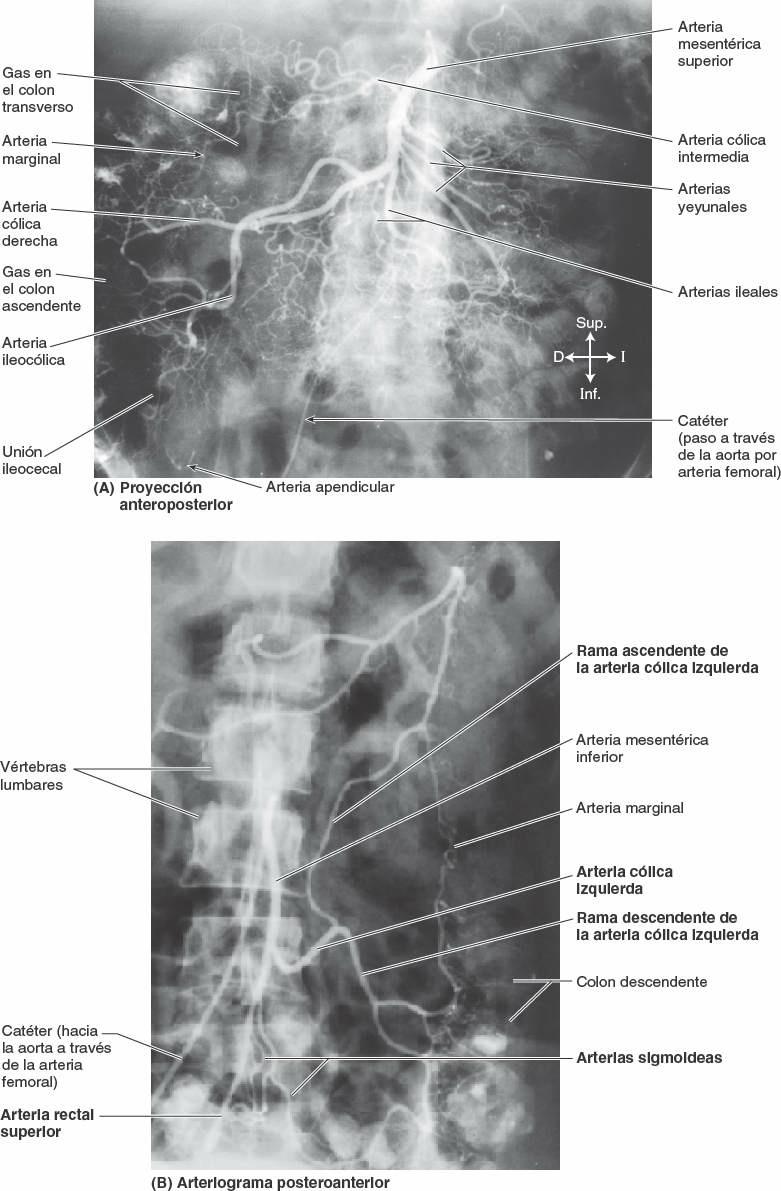

La arteria mesentérica superior (AMS) irriga el yeyuno y el íleon a través de arterias yeyunales e ileales (fig. 5-49 B).

Normalmente la AMS nace de la aorta abdominal a nivel de la vértebra L1, aproximadamente 1 cm inferior al tronco celíaco, y discurre entre las hojas del mesenterio, enviando 15 a 18 ramas al yeyuno y al íleon (figs. 5-54 y 5-55). Las arterias se unen para formar asas o arcos, las arcadas arteriales, que dan origen a unas arterias rectas, los vasos rectos (figs. 5-48 B y 5-49 B).

La irrigación arterial del colon ascendente y de la flexura cólica derecha procede de ramas de la AMS, la arteria ileocólica y la arteria cólica derecha (figs. 5-54 y 5-55; tabla 5-9). Estas arterias se anastomosan entre sí y con la rama derecha de la arteria cólica media, la primera de una serie de arcadas anastomóticas que se continúa con las arterias cólica izquierda y sigmoidea para formar un conducto arterial continuo, la arteria marginal (arteria yuxtacólica). Esta arteria discurre paralela al colon durante toda su longitud, junto a su borde mesentérico.

La irrigación arterial del colon transverso procede principalmente de la arteria cólica media (figs. 5-54 y 5-55; tabla 5-9), una rama de la AMS. Sin embargo, también puede estar irrigado, en grado diverso, por las arterias cólicas derecha e izquierda a través de anastomosis, componentes de la serie de arcadas anastomóticas que colectivamente constituyen la arteria marginal (de Drummond, arteria yuxtacólica).

La irrigación arterial del colon descendente y el colon sigmoideo procede de las arterias sigmoideas y cólica izquierda, ramas de la arteria mesentérica inferior (AMI) (fig. 5-54; tabla 5-9). De este modo, aproximadamente en la flexura cólica izquierda, se produce la segunda transición importante en la irrigación sanguínea de la porción abdominal del tubo digestivo: la AMS aporta sangre a la porción proximal a la flexura (derivada del intestino medio embrionario), y la AMI irriga la porción distal a este punto (derivada del intestino posterior embrionario). Durante la resección quirúrgica del colon, es importante visualizar la anastomosis entre la AMS y la AMI para garantizar la irrigación sanguínea continua. Las arterias sigmoideas descienden oblicuamente hacia la izquierda, donde se dividen en ramas ascendentes y descendentes. La rama superior de la arteria sigmoidea más superior se anastomosa con la rama descendente de la arteria cólica izquierda, formando así parte de la arteria marginal. El drenaje venoso del colon descendente y el colon sigmoideo se realiza en la vena mesentérica inferior y desemboca habitualmente en la vena esplénica, y luego en la vena porta hepática, de camino hacia el hígado (figs. 5-56 A y 5-75 B).